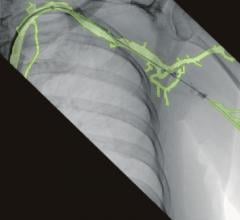

December 6, 2012 — Giving clinicians a more complete picture while improving safety during interventional procedures, Toshiba America Medical Systems Inc. introduces Spot Fluoroscopy for its Infinix-i angiography systems. Enabling quicker diagnoses and lower dose, clinicians can observe a target region of anatomy using Spot Fluoro’s live fluoroscopy while viewing the last image hold (LIH) surrounding area.

“Spot Fluoroscopy is like having an adjustable spot light over the reference LIH image, helping to reduce dose exposure and allowing the clinician to view the critical region of interest and the surrounding area at the same time,” said Stephen Bumb, director, X-ray Vascular Business Unit, Toshiba. “This unique type of unconventional collimation streamlines interventional procedures and reduces radiation exposure to both clinicians and patients, making exams safer for everyone involved.”